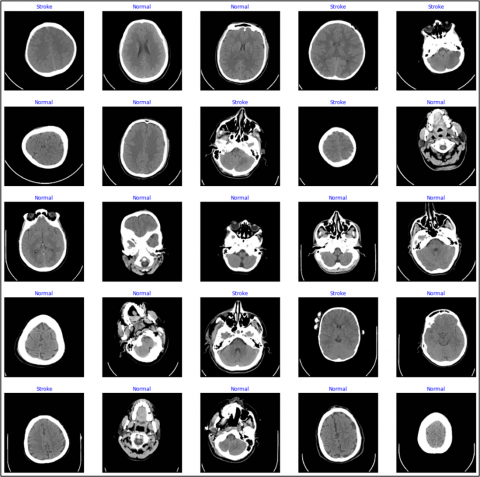

The second experiment involves deep learning in a convolutional neural network. The dataset used in this paper is MRI images, which include images of two types of people: normal and stroke brain cases [15]. The data set contains 2515 images, divided into 1551 normal images and 964 images of cerebral hemorrhage. The images were recorded in a resolution format of up to 256×256 pixels for each image. Figure 1 describes a different image for normal cases and injured cases, which were also obtained from the Kaggle website [15].

Figure 1. Dataset 2 (normal and stroke brain) images